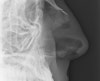

1. Radiology

(1) This image shows an irregular fracture line passing across the mandible on the left. Careful inspection of the mandibular outline shows a second fracture at the mental symphysis.

(2) Both fractures are again seen on the mandibular view.